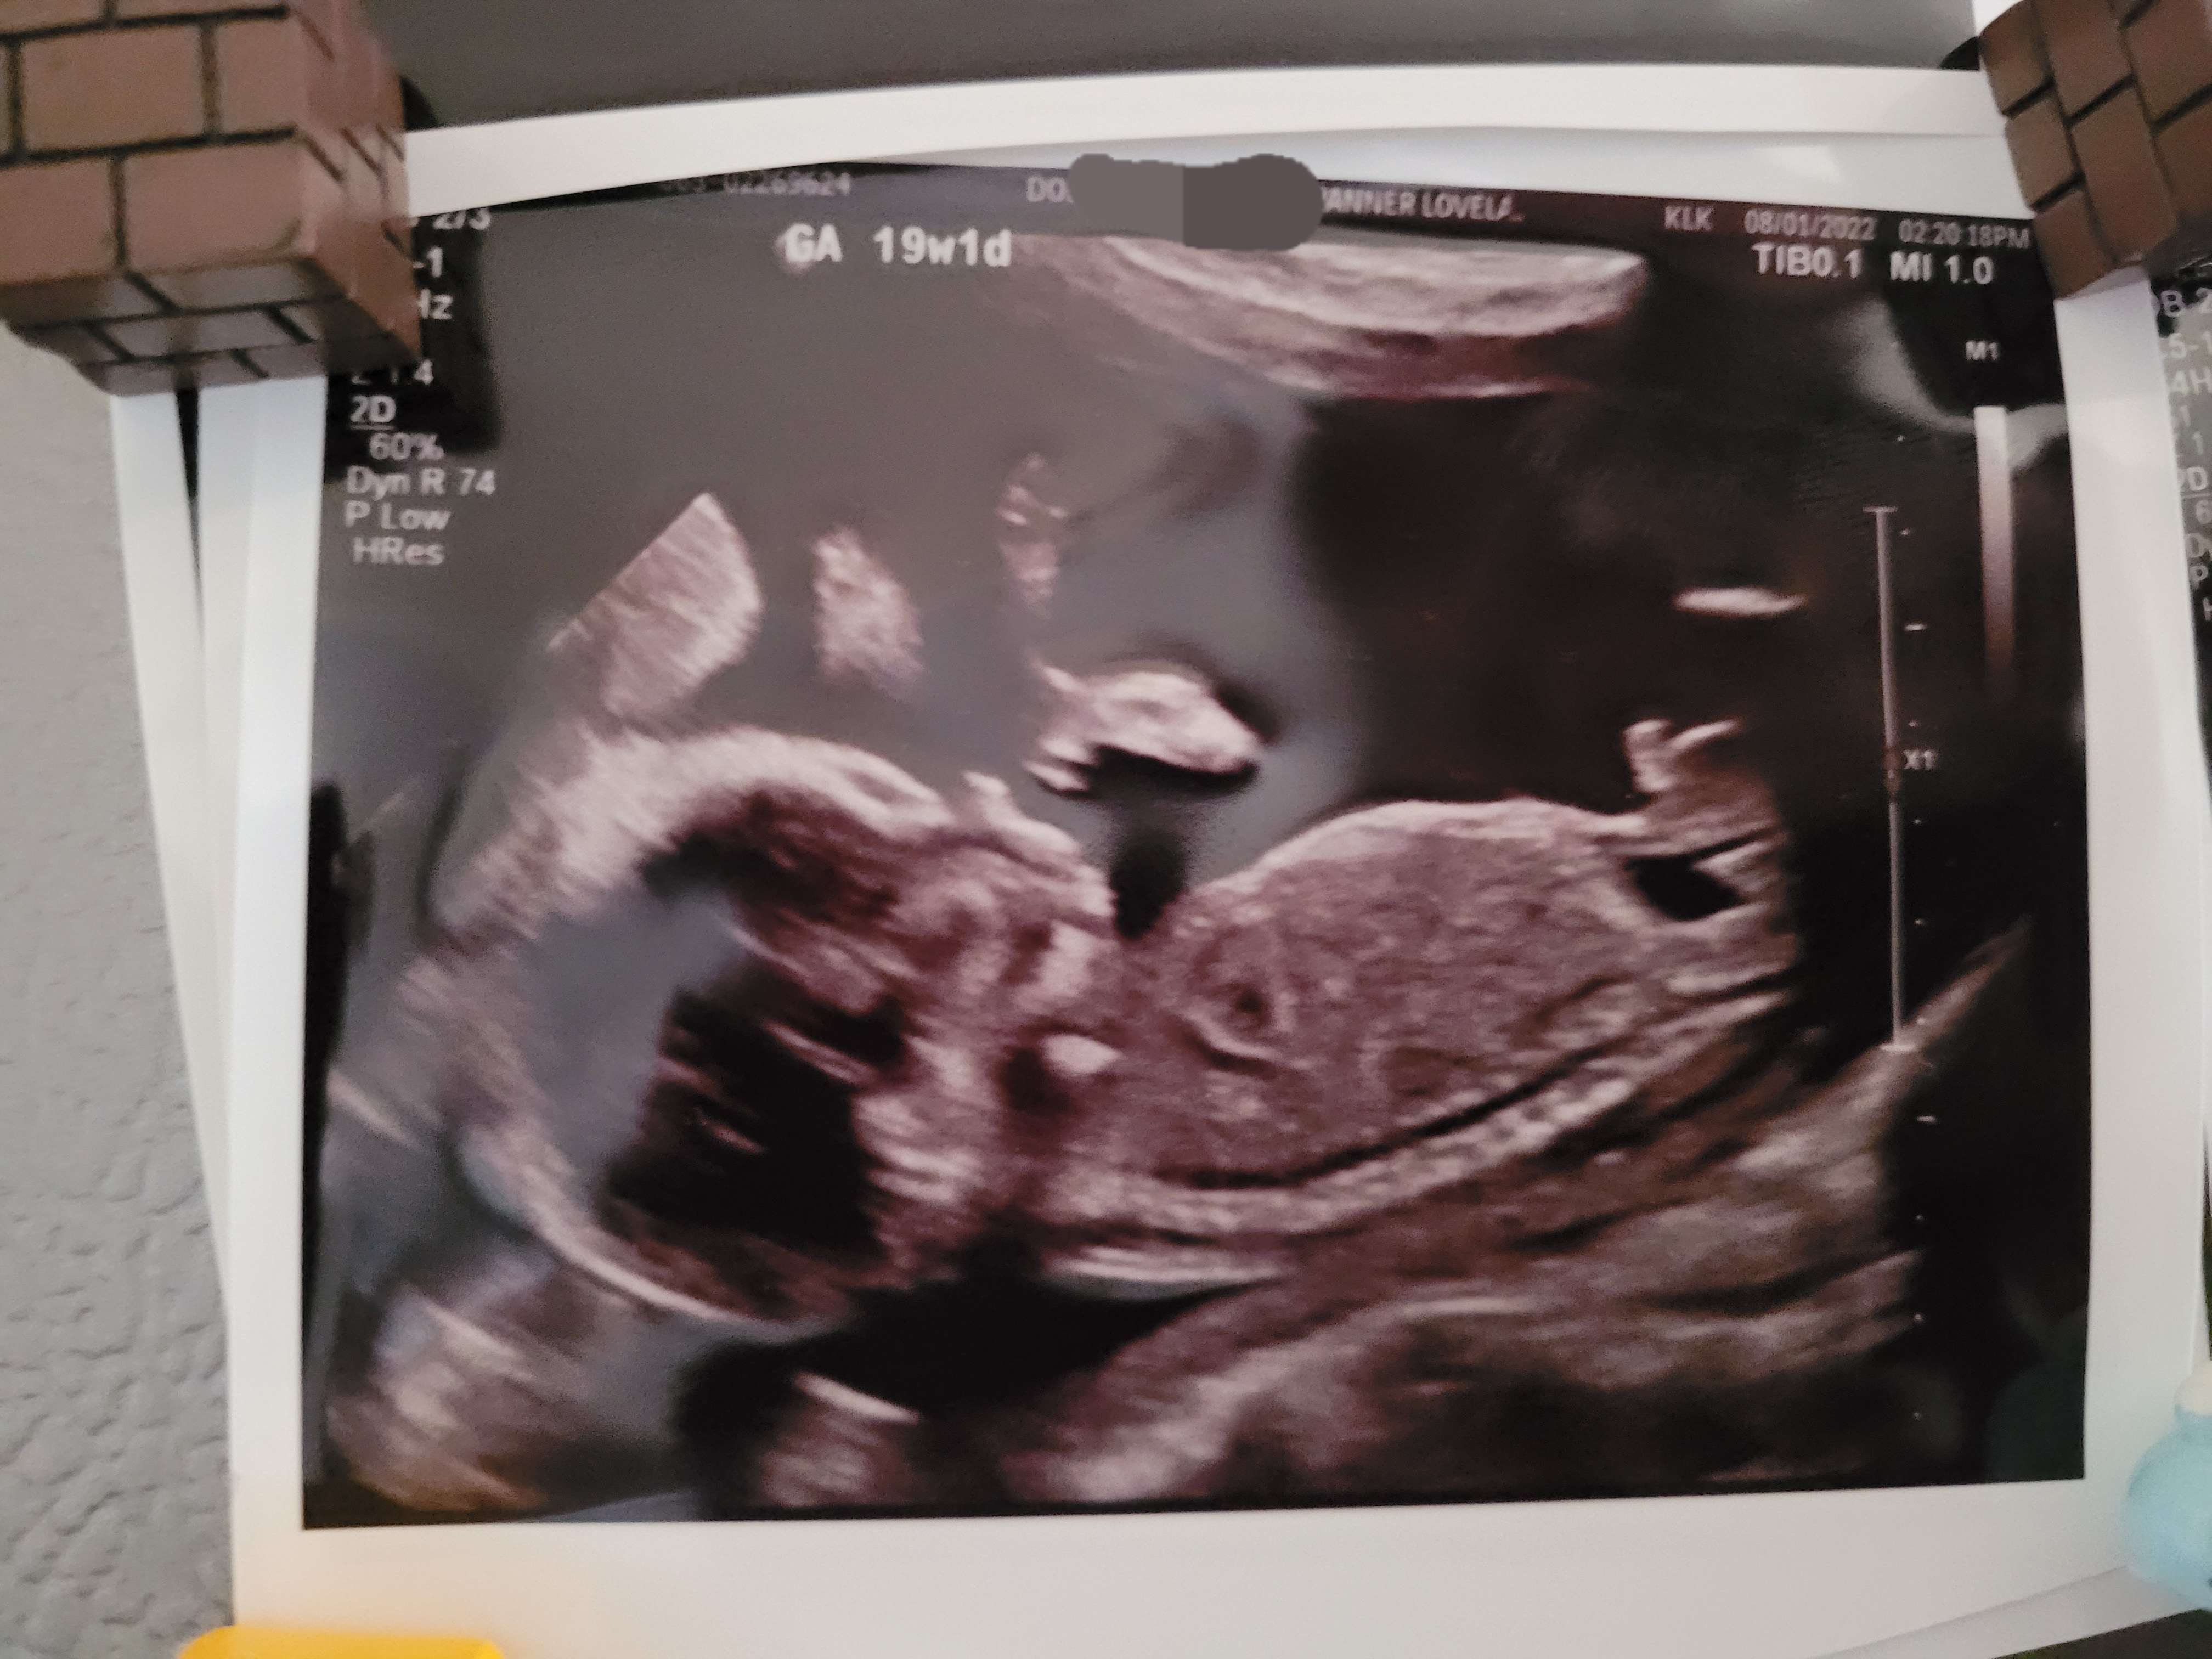

Cato Emery Tran born 12/27/2022 at 8:30pm at Banner Medical Center Fort Collins. Baby weight 6lbs 13oz. Height 19.5 inches. Labor was pretty easy as he was delivered about 3 hours after check-in at the hospital. Mom and baby are doing well. Missed his due date (Christmas) by two days.

Due Christmas Day 2022